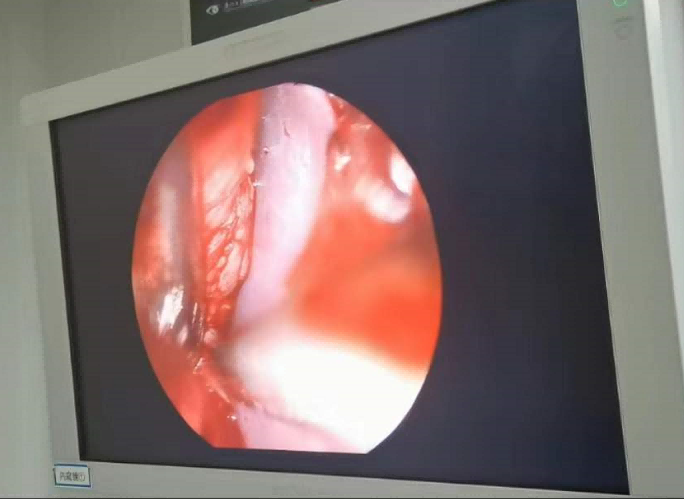

送到廈門眼科中心的時(shí)候,林老師受傷的左眼還在流血。眼整形科的鄧?yán)っ鞲敝魅吾t(yī)師緊急為他安排了“內(nèi)鏡下眶骨折修補(bǔ)+鈦網(wǎng)鈦釘植入術(shù)”。

圖為:內(nèi)鏡下眼眶骨折修補(bǔ)術(shù)

手術(shù)過程中林老師還出現(xiàn)了驚險(xiǎn)的眼球后大出血,還好鄧?yán)っ饔诰o急之中穩(wěn)住了病情,并順利完成了手術(shù)。術(shù)后第二天,林老師的術(shù)后反應(yīng)就很輕,恢復(fù)良好,他一邊感謝著鄧?yán)っ鞯?ldquo;救命之恩”,一邊自嘲著自己示范了個(gè)“反面教材”。